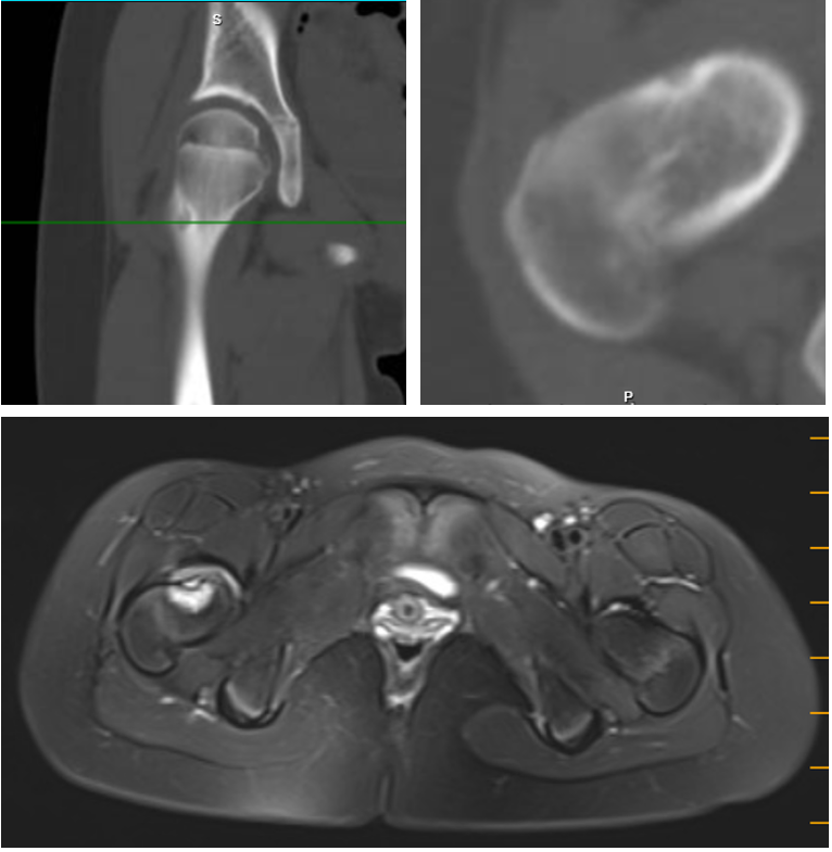

读片:CT可见右侧股骨颈前方皮质的类圆形瘤巢,直径约8mm,边缘可见骨质硬化。MRI T2象示围绕瘤巢的高信号水肿带。